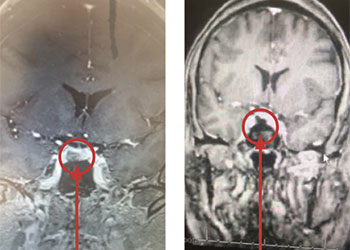

Pituitary Tumor with Cushing’s Disease

Author: Michael Brisman M.D., F.A.C.S., Read More!